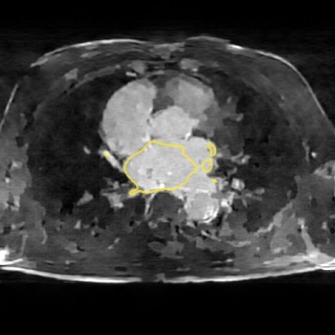

The following images show more samples for 8-fold undersampling. For each of the seven patients of the test set, a random slice showing the left atrium was selected. The contour of the predicted segmentation of left atrium is shown in yellow, the contour of the ground truth segmentation in red.